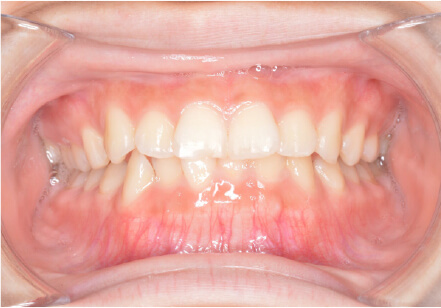

叢生の症例

9歳

女性

相談内容

マイオスマイルからの移行

カウンセリング・診断結果

上11捻転、上33スペース不足、インビザで歯列矯正

治療内容・方法

全額アライナー矯正 クリアコレクト

術後の経過・現在の様子

リンガルアーチ使用

治療のリスク

痛み・歯根吸収・歯肉退縮・虫歯・後戻り

費用・治療期間

(マウスピース矯正のみ)440,000円+220,000円 月々27,500円、9ヶ月+myo1年10ヶ